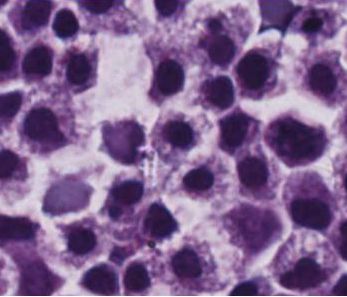

免疫系统的自然杀伤(NK)细胞识别并攻击两种主要类型的危险细胞:病毒感染的细胞和受癌症影响的细胞...

这种称为“嵌合体抗原受体T细胞疗法”(CAR-T)的免疫疗法从患者身上收集免疫攻击性T细胞,并对它们进行遗传修饰以识别表面上的特定肿瘤...

大多数CAR-T细胞疗法都需要靶向癌细胞特异性抗原,当前,有新方法靶向肿瘤周围的环境...